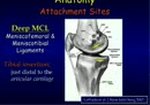

PCL Reconstruction in an Athlete with a Multiligament Knee Injury

Dr. Alaia from NYU Langone Orthopedics demonstrates the technique for PCL reconstruction in an athlete ...

read more ↘ with a multiligament knee injury.